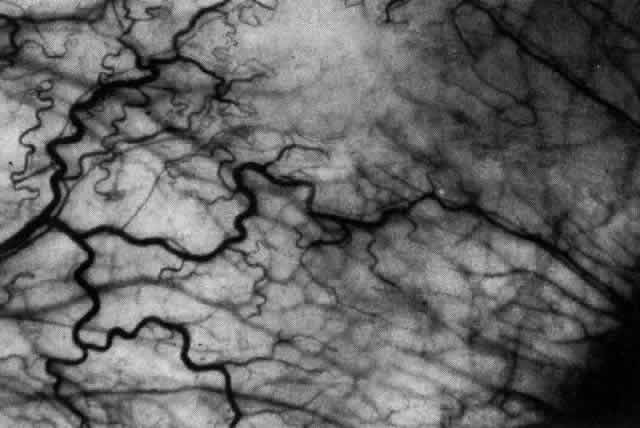

The object of slit lamp examination is to determine the depth and nature of scleral and episcleral conditions and the presence of corneal changes. The changes seen are drawn in the records. With the use of diffuse light with a neutral density filter, the vascular networks of both eyes are examined in detail to determine the layer in which the vessels show maximum congestion, the infiltration of episcleral tissues, and the edema of sclera, episclera, or subconjunctival space. Slit lamp examination is also used to ascertain the nature and depth of any corneal changes; the presence of scleral edema (for which it may be necessary to blanch the superficial tissues with epinephrine 1:1000 or phenylephrine 10%); the nature of any episcleral infiltration or mass; and the presence of cells in the anterior chamber or vitreous and posterior synechiae. The red-free (green) filter is extremely valuable in confirming the areas of maximum congestion and whether any areas are totally avascular. Because this is an important physical sign and is easily missed, examination in red-free light should be routinely performed. The green light brings the vessels into very sharp contrast with the background and enables the position of maximum inflammation to be determined with certainty. It also enables the paths and configurations of the vessels to be followed and will show lymphocytic infiltration of the episcleral tissue as yellow spots; this often indicates that the condition is more extensive than previously supposed (Fig. 8).

Fig. 8. Examination in red-free light. Blood vessels brought into sharp contrast reveal areas of lymphocytic infiltration in episcleral tissues, in this case due to herpes simplex virus.